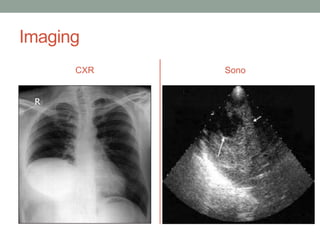

Imaging - SONO

• currently the primary

diagnostic technique

and has diagnostic

accuracy of 90%.

• This scan is of a

multiloculated cyst.

Gharbi’s Classification